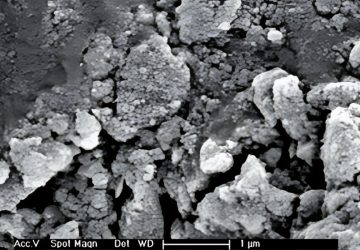

En endodontie, la réussite du traitement radiculaire ne dépend pas uniquement de l'instrumentation mécaniqu...